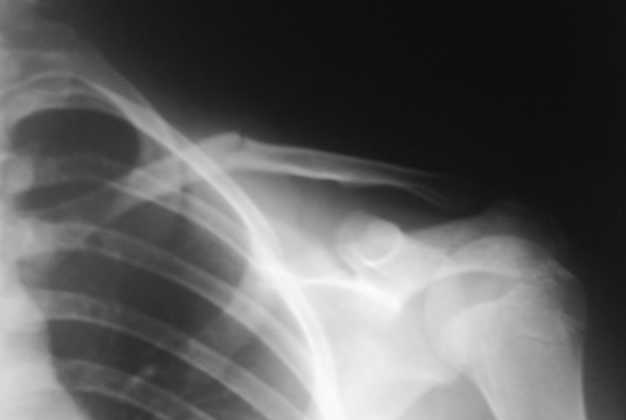

Девочка 14 лет, на даче упала с турника 05-07-08, в наш травмпункт обратились на следующий день - Диагноз: Закрытый перлом диафиза левой ключицы. Дежурным травматологом наложена 8-образная гипсовая повязка. На следующий день, родители привели девочку с жалобами на давление в левом надплечье и онемение правого предплечья и 1,2, 3-го пальцев кисти.

Мной была немедленно снята наложенная накануне повязка, и заменена на марлевую Дезо. 09-07-го, Дезо заменена на "косыночную" повязку.Сегодня произведен контрольный снимок -На сегодняшний день сохраняется онемение 1-3 пальцев.